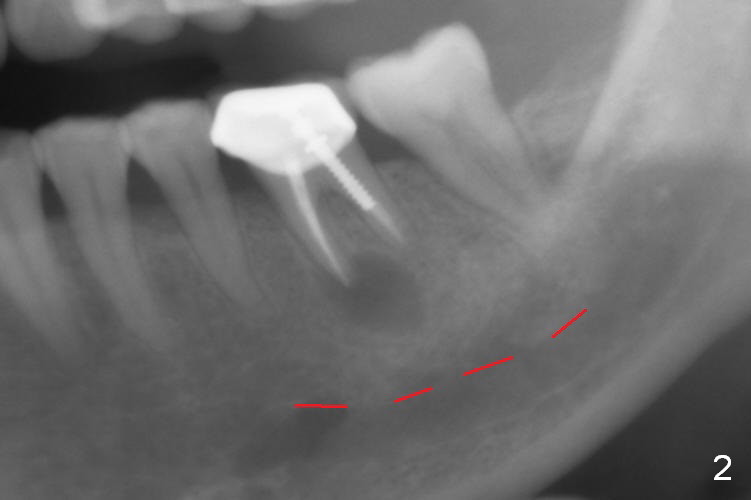

A 58-year-old lady has a long-standing periapical lesion with several episodes of acute infection (Fig.1-3, taken 10, 9 and 2 years ago, respectively). Explore the socket for size and wall integrity (Clindamycin). If the bony defect is not extensive, place a longest implant (18 mm bone-level, 20 mm tissue-level) with moderate diameter (5.5, 6 mm). Otherwise use a shorter, but wider tapered implant (7x12 mm (bone-level), 7 or 8x17 mm (tissue-level)). If the socket is extremely large, consider using 7 or 8 x20 mm cylindrical tissue-level implant. Use Bicon 2 mm pilot drill with extension to measure the socket depth and obtain 3-6 mm new bone or until 20 mm (gingival margin). Take PA. The 1st option is to use UF 3-4.7x18 mm drills at 50 RPM. Make sure that the depth is reached (septum crestal level) and check osteotomy wall integrity after each drill. Then place a 5 or 5.5x16 or 18 mm implant (Fig.6). The 2nd and 3rd options are shown in Fig.4 and 5. Due to severe infection and pain, a shorter implant is placed.